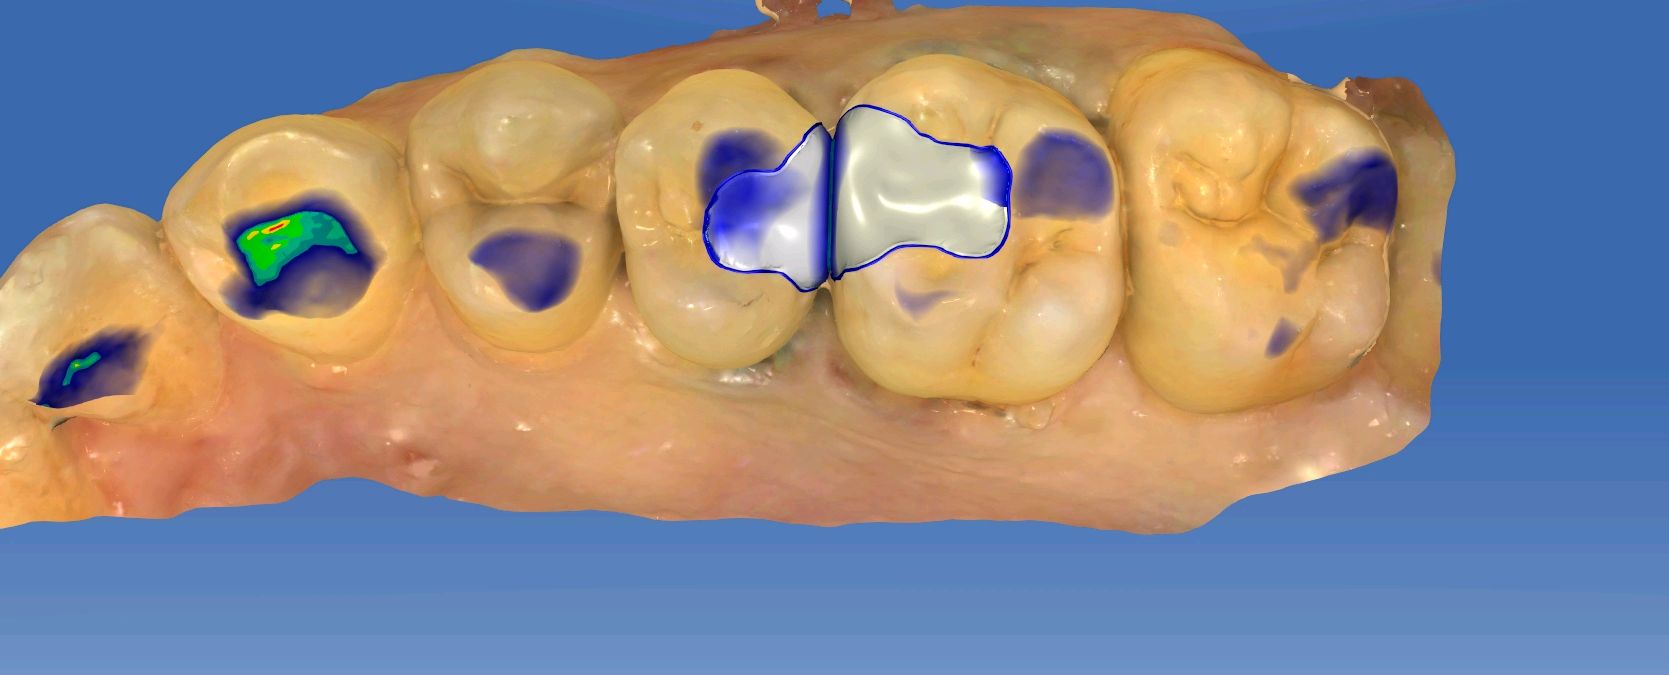

患者男,28岁。主诉左上后牙食物嵌塞。检查发现25、26邻面龋坏,色泽发黑,质硬 冷测正常,余无特殊。治疗计划:去腐后嵌体修复。

图片发自160App

术前